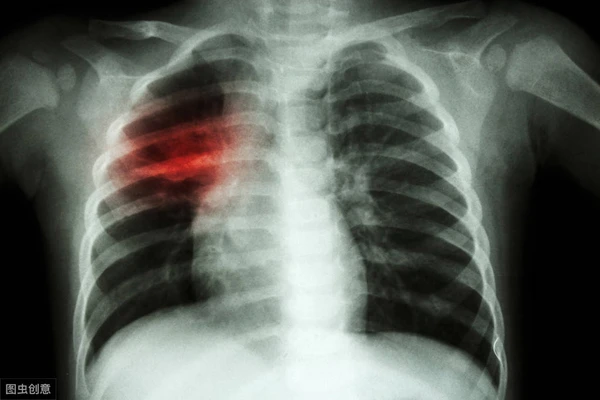

Anh Vương năm nay 43 tuổi nhưng có thời gian hút thuốc lá hơn 20 năm. Gần đây, Vương có triệu chứng tức ngực, khó thở - đặc biệt vào buổi sáng khi mới thức dậy. Kể với người nhà, anh được khuyên nên đến viện khám. Kết quả kiểm tra cho thấy, Vương mắc ung thư phổi giai đoạn cuối. (Ảnh: Sohu, minh họa)